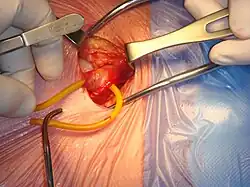

Open surgical repair of a right inguinal hernia | |

Open hernia repair

All techniques involve an approximate 10-cm incision in the groin. Once exposed, the hernia sac is returned to the abdominal cavity or excised and the abdominal wall is very often reinforced with mesh.[11] There are many techniques that do not utilize mesh and have their own situations where they are preferable.[25][17]